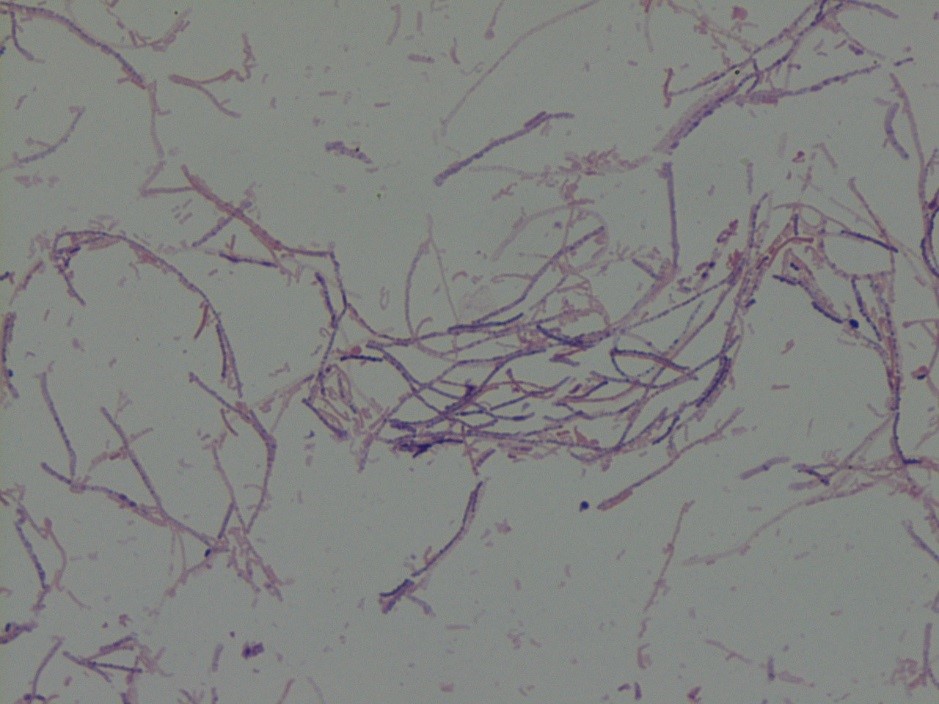

The patient’s tissue Gram stain was notable for 2+ WBCs (PMNs) and 4+ gram negative rods. The predominant organism grew on 5% sheep blood and chocolate agars but there was no growth on the MacConkey agar (Image 1).